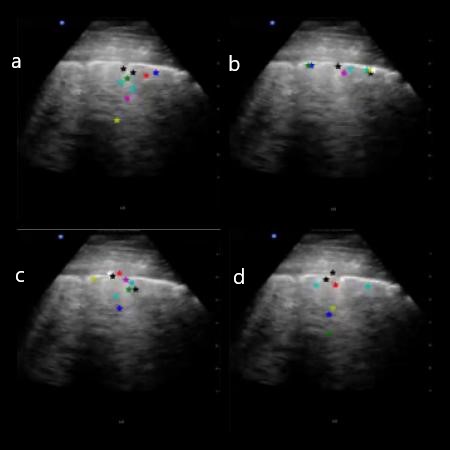

3.2 Performance of the proposed keypoint detection with attention

We evaluated the performance of the proposed keypoint detection with attention mechanism on the LUS and WUS datasets in terms of Specificity (SP) and Sensitivity (SN) in identifying relevant keypoints. The output of the transporter networks on LUS and WUS images are as shown in Figures 8 and 9. The four columns in the plots represent the cases with only horizontal IRT, only vertical IRT, combined IRT with attention and the vanilla transporter outputs. It is evident from the figures that the proposed attention based scheme significantly improves the localization of keypoints within the desired landmarks. In WUS images, the network also identified points near the bone discontinuity indicating fracture with out any explicit supervised training.

Refer to caption

Figure 8: Output of different Transporter networks on LUS frames

Figure 9: Output of different Transporter networks on WUS frames

In order to quantify the detection performance of the proposed approach, the estimated keypoints are compared against a manual segmented ground truth. In order to improve the performance of the keypoint detection particularly due to display labels, frame averaging has also been employed (note that frame averaging correction was not used during the training process). Frame averaging correction involves extracting average/median frame from the US video sequence and masking out the average/median frame from individual frames from the US video sequence, this correction helps in reducing the stationary but noisy artefacts from the US video frames. In fractured and non-fractured wrists, the proposed approach correctly identified the top portion of the bone with multiple keypoints (refer Figure 9). In fractured wrists (third row in Figure 9, the network was able to track keypoints near the fracture. The performance metrics on 58 manually labelled WUS videos are shown in Table 1. In the case of LUS, binary segmentation data of LUS frames with landmarks like Pleura, A lines and B lines was used to compare the performance metrics. The proposed approach detected these landmarks efficiently and the performance metrics on 1000 manually labelled LUS frames are shown in Table 2. Additionally, to quantify the performance of the proposed unsupervised key point learning approach on Lung Ultrasound data further, the accuracy of detecting most common landmark, i.e, pleura, has been evaluated. The results show that the proposed approach has been successful in correctly detecting pleura in 950 frames out of 1081 frames which shows an accuracy of 91.8%. The network was also evaluated on LUS segmentation data by considering the GradCam heatmap generated by KeyNet to be predicted segmentation with the Dice coefficient for pleural line detection, which was obtained to be 0.87.